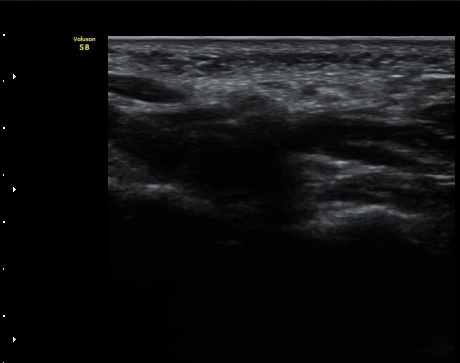

ŽÃËÀÚ¸¦ ¸»´ÜÀ¸·Î À̵¿ÇÏ´Ï °¥°í¸®»À ³»Ãø¿¡¼­ Ç¥Ãþ°¨°¢½Å°æ°ú ½ÉºÎ¿îµ¿½Å°æÀÌ °üÂûµÈ´Ù(»çÁø 3).

ŽÃËÀÚ¸¦ Á¶±Ý ´õ ¸»´ÜÀ¸·Î À̵¿ÇÏ´Ï Ã´°ñ½Å°æ ½ÉºÎ¿îµ¿°¡ÁöÀÇ ºÎÁ¾ÀÌ °üÂûµÇ°í ½Å°æ ¿äÃøÀ¸·Î Àú¿¡ÄÚ

¿øÇüÀÇ Á¾±«°¡ °üÂûµÈ´Ù(»çÁø 4, 5).

ŽÃËÀÚ¸¦ Á¾±«ÀÇ Á¾´Ü¸éÀ¸·Î À§Ä¡ÇÏ´Ï ÀÌÁúÀûÀÎ ¿¡ÄÚ¸¦ º¸À̴ Ÿ¿øÇüÀÇ Á¾±«°ú °üÂûµÇ°í

Á¾±« Ç¥ÃþÀ¸·Î Á¤Áß½Å°æ °¡Áö°¡ °üÂûµÈ´Ù.

ô°ñ½Å°æ ½ÉºÎ¿îµ¿°¡Áö´Â Á¾±«ÀÇ ½ÉÃþ¿¡ À§Ä¡ÇÒ °ÍÀ¸·Î ÆÇ´ÜµÇ´Âµ¥ ±¸ºÐµÇÁö ¾Ê´Â´Ù(»çÁø 6).